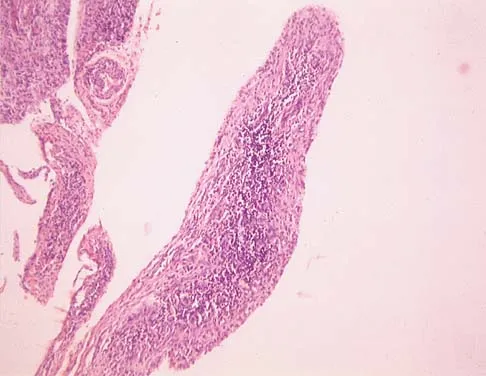

A 14-year-old boy reports progressive right wrist pain. Radiographs are shown in Figure 3a, and a photomicrograph is shown in Figure 3b. What is the most likely diagnosis?

Explanation